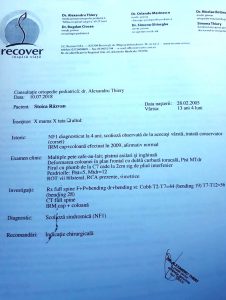

Răzvan Ioan Stoica are o curbură a coloanei vertebrale de 37 grade, iar aceasta se accentuează pe măsura trecerii timpului. Pentru ca lucrurile să nu se agraveze, el are nevoie cât mai urgent de o operație.

Răzvan a fost diagnosticat cu această boală de la vârsta de 4 ani și a purtat permanent un corset. Lucrurile s-au agravat însă, iar acum se impune intervenția chirurgicală.